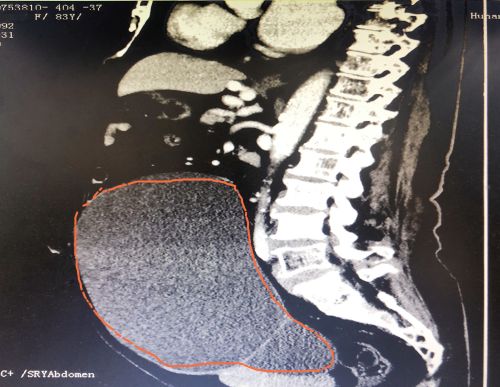

ct显示,肿瘤几乎占据老人整个盆腔和腹腔。

2021年1029日,彭娭毑住进湖南省人民医院妇科病房。完善相关检查发现,巨大的肿瘤几乎占据她整个盆腔和腹腔,并且压迫肠道和膀胱,这也是老人尿频的原因。与此同时,术前血液检查发现了异常——全系细胞减少,进一步骨髓穿刺结果为:可疑B细胞淋巴瘤骨髓浸润。